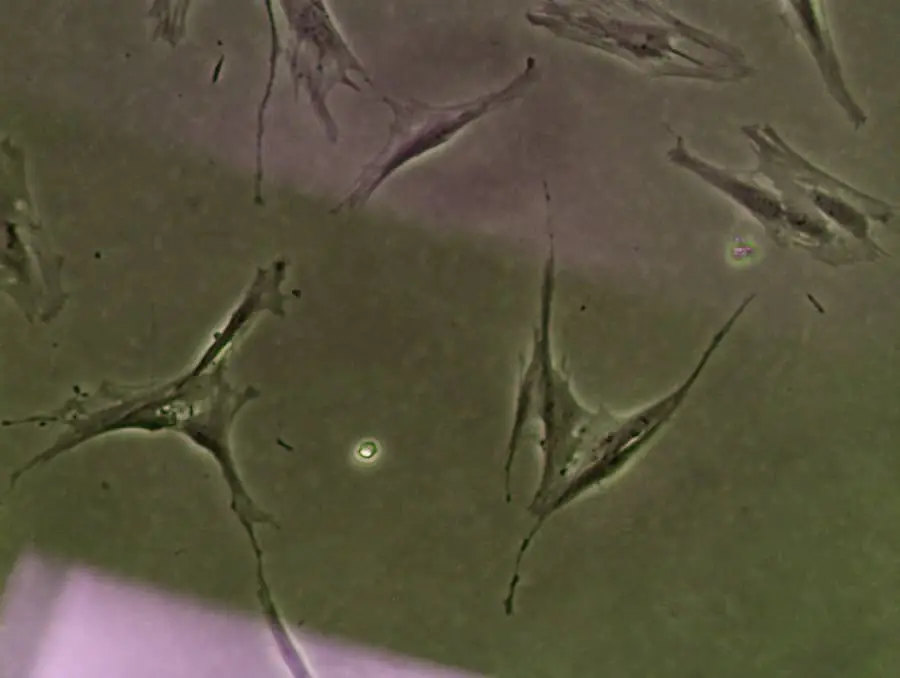

間充質基質細胞 (MSC) 也稱為多能基質細胞,是一種存在于多種組織中的細胞,包括骨髓、脂肪、牙齦、外周血以及胎盤和臍帶。它們通常被稱為“基質”,因為它們位于組織支持網絡中,為其他細胞提供結構和支持。然而,它們的作用不僅僅是支持。?

對這些干細胞的進一步研究表明,MSC可以分化成多種細胞類型,包括骨、軟骨、脂肪、神經和肌肉細胞。這使它們成為再生醫學的有希望的候選對象,具有治療各種疾病和損傷的潛力。在本文中,我們將全面回答“間充質干細胞療法如何起作用?”這個問題。